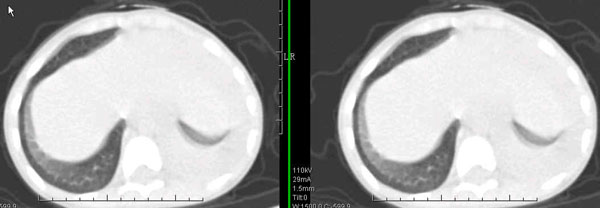

男孩,4岁,发热咳嗽4天。

下面补充ct图片:

此病人是我接手的,发热、咳嗽来做胸透,透视见左侧肺野大部密实,纵隔、心影明显左移,呼吸示纵隔摆动、膈肌矛盾运动(透视下采集了几幅图片),左肺动度明显减弱。询问病人家长,没有吃花生米等呛咳史。由于其影像特征明显,当时诊断:考虑左侧支气管异物并阻塞性肺不张、肺炎。

病人去上级医院支气管镜取出了异物。今天询问上级医院耳鼻喉科主任(是我同学),得知病人异物为胶冻样合并有少许白色粉末,后小儿说晚上喝药片时呛咳过,考虑当时为药片阻塞;另外支气管镜检发现小儿左侧支气管发育略窄,经住院抗炎治疗,现病人基本康复。

多谢各位关注及精彩点评!追踪病人结果时才知道还做过ct检查!对不起!有点晚了,刚刚下载,上传供大家参考!